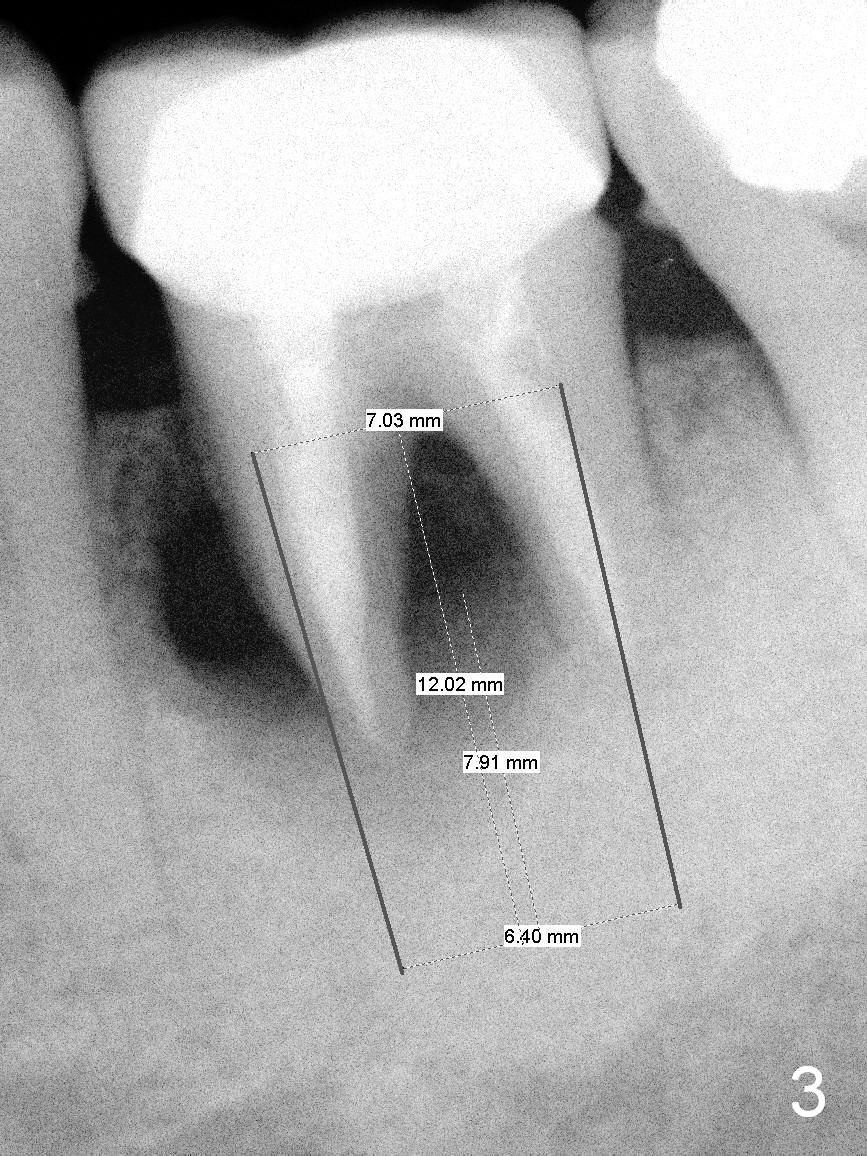

The tooth #19 of a 54-year-old man (FJ) looked normal 2.5 years ago (Fig.1). The patient returns because of 3 fistulae developing around the mesial root of the tooth. Recent PA shows a large radiaolucent defect (Fig.2,3). To place an implant in the middle of the edentulous space, initial osteotomy should be distal because of the large mesial defect.

After extraction, the socket will be packed with gauze saturated with 2% Xylocaine/1:50,000 Epinephrine. If the septum is present (Fig.4 S), the initial osteotomy starts obliquely on the distal surface of the septum (Fig.5). If the septum is absent, the osteotomy is initiated in the distal bottom of the socket (Fig.6, slightly lingual): 3-6 mm beyond the initial level. A calibrated parallel pin is inserted (Fig.7 green line); the sensor block is placed as deep as possible (white outline) to confirm clearance between the tip of the osteotomy and the superior border of the Inferior Alveolar Canal (yellow dashed line).